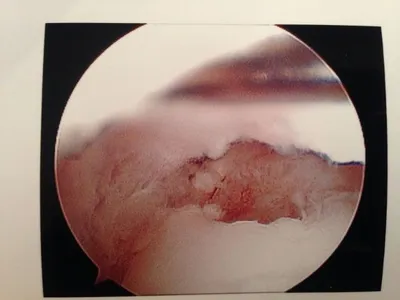

A series of intraop ankle arthroscopy pics of synovial chondromatosis with OCD talus and tibia and microfracture.

Pic of an OCD in the talar dome due to pressure from the nodule.

Pic after microfracture and debridement of above OCD.